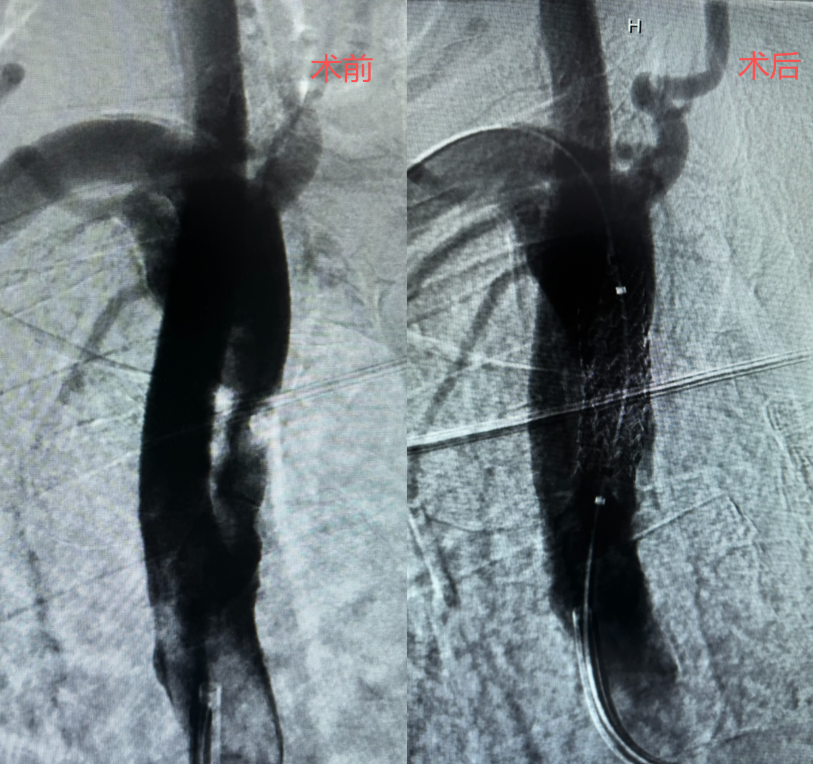

此次接受手术的患者秦某,男,74岁,因脑梗死入住中风科,入院后,科室医疗团队详细询问病史、全面查体,完善数字减影血管造影(DSA),最终确诊为右侧锁骨下内动脉起始部重度狭窄,狭窄程度达90%以上,同时伴随锁骨下动脉盗血综合征,若不及时干预,病情持续进展可能引发再次脑梗死、上肢缺血坏死等严重后果,危及患者生命健康,有非常明确的手术指征。

手术过程中,中风科介入团队在DSA(数字减影血管造影)引导下,精准穿刺患者股动脉,首先为患者进行狭窄部位造影,选取最好的工作角度,精准操控导丝、导管顺利通过狭窄病变血管,并依次完成球囊预扩张,运用“球囊穿梭”技术送高导引导管,再以“特洛伊木马”技术输送支架至血管狭窄处,支架精准定位与释放,全程操作精准流畅。术中实时造影可见狭窄部位程度改善,患者锁骨下动脉狭窄段完全扩张,支架位置精准、贴壁良好,血流通畅,盗血现象即刻消失,双侧上肢血压恢复对称,手术圆满成功。